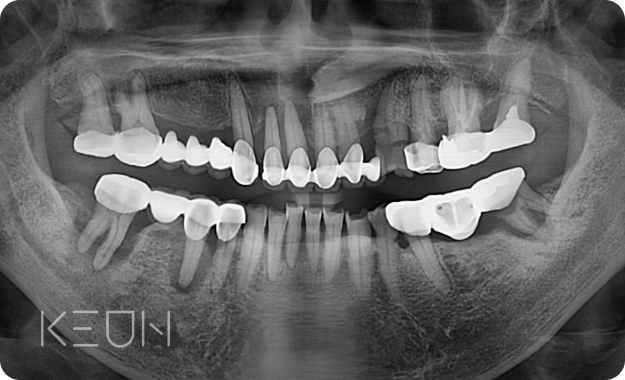

뼈이식 임플란트 전후사진.

- Before

- After

*모든 치료전/후 사진은 환자분의 동의하에 촬영 및 게시되었습니다.